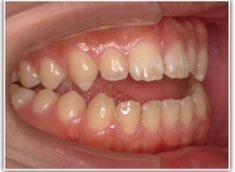

開咬(かいこう:オープンバイト)ケース

治療法:表の矯正(T21ブラケット)

(インプラントアンカーや外科矯正は行わず、エラスティックと機能訓練のみ)

治療前